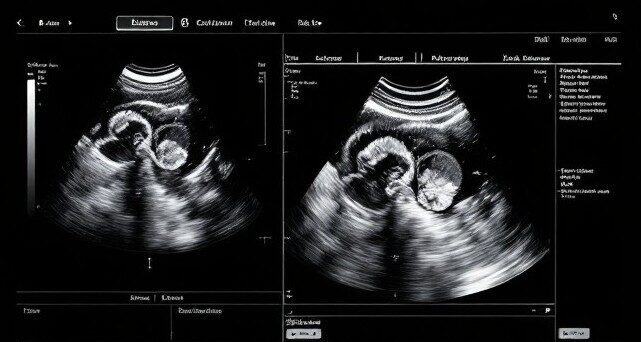

Our Radiology Department delivers comprehensive imaging services to support diagnosis, treatment planning, and patient safety. Open Monday to Friday from 8:00 AM to 6:00 PM, we employ the latest technology and experienced professionals to ensure accurate, timely results. Imaging Modalities and Services X-Ray: Computer Radiography – chest, extremities, spine, abdomen and others. Ultrasound: Abdominal, pelvic,…